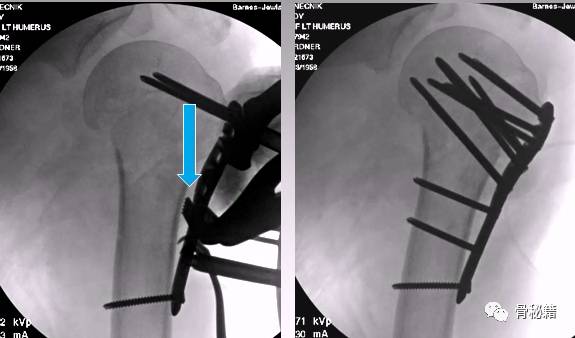

病例1

4部分骨折

正位的翘拨复位

腋位的翘拨复位

解剖钢板与提拉螺钉的复位

需要注意 不要应用过度提拉 使得内侧肱骨距过复位

注意完成内侧支撑和内外翻的复位

在此病例中,为了复位良好,舍弃了肱骨近端与钢板贴服